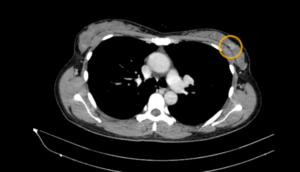

Ca lâm sàng: Phát hiện, chẩn đoán giai đoạn sớm một bệnh nhân mắc đồng thời ung thư phổi và ung thư tuyến giáp tại Trung tâm Y học hạt nhân và Ung bướu, bệnh viện Bạch Mai

Ca lâm sàng: Phát hiện, chẩn đoán giai đoạn sớm một bệnh nhân mắc đồng thời ung thư phổi và ung thư tuyến giáp tại Trung tâm Y học hạt nhân và Ung bướu, bệnh viện Bạch Mai GS. TS Mai Trọng Khoa, PGS. TS Phạm Cẩm Phương, TS. Phạm...